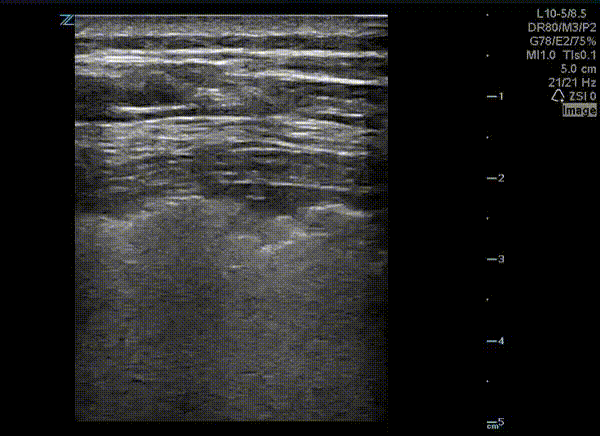

This is a lung ultrasound performed on a patient with COVID-19. The patient had no prior pulmonary disease. They presented with mild tachypnea and hypoxia. A chest x-ray revealed diffuse interstitial and patchy airspace densities. This ultrasound clip shown demonstrates an irregular pleural line with subpleural nodular consolidation and waterfall B-lines. Image courtesy of Dr. Eric Abrams (@eabramsMD)